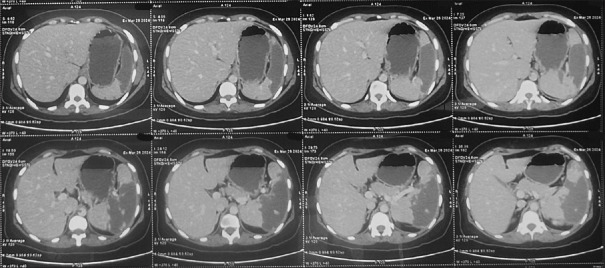

Tuberculosis (TB) continues to be a major global health concern, particularly in regions where it is endemic. While TB commonly affects the lungs and extrapulmonary sites, its presentation as vasculitis leading to multiple organ infarcts is an extremely rare phenomenon. This case report describes a 34-year-old female who developed simultaneous infarctions in the spleen, kidney, and lungs due to TB-related vasculitis. The diagnosis was established through clinical presentation, imaging studies, and confirmation of Mycobacterium tuberculosis via sputum CBNAAT. The patient was successfully managed with antitubercular therapy (ATT) and corticosteroids, demonstrating significant clinical improvement. The rarity of multisystem infarcts caused by TB underscores the importance of considering tuberculous vasculitis in the differential diagnosis of unexplained infarcts, particularly in endemic regions. Early detection and timely intervention are crucial in preventing severe complications and improving patient outcomes.